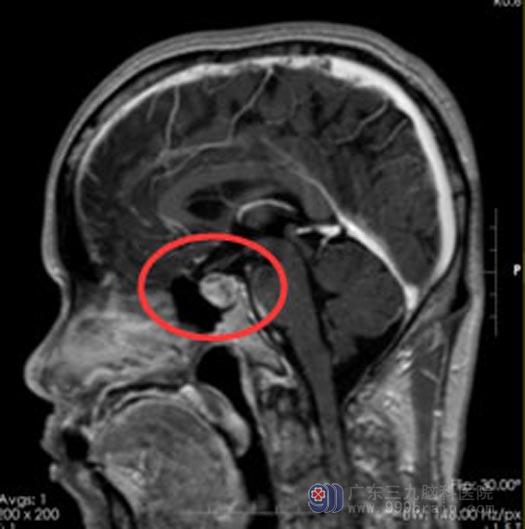

直至8月份,头痛头晕症状加重,才想起到医院行MRI检查,结果显示:鞍区占位,考虑垂体瘤。广东三九脑科医院进一步检查发现:鞍内偏左侧示类圆形占位性病变,范围约15.9mm×14.6mm×19.4mm。

手术前